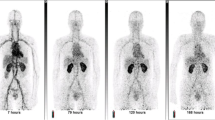

Tissue-specific uptake of nanoparticle-based probe: 64Cu-NOTA-D20

The average time from 64Cu-NOTA-D20 radiotracer injection to start of PET imaging was 2 min, 25 s. Average probe circulation in blood and tissue-specific uptake were not different between injection methods for tumor, kidney, spleen, lung, or liver (Fig. 6A). Similarly, results from dynamic PET quantification demonstrate equivalent nanoparticle-based probe distribution in blood, tumor, kidney, spleen, lung, and liver measured over time between JV and RO injection methods (Fig. 6B–G). Despite biological differences in tumors between JV- and RO-injected mice, tumor uptake of 64Cu-NOTA-D20 was not different between the groups, although heterogeneous intratumoral probe distribution can be observed in representative PET-CT images shown in Fig. 6H. Although dextran nanoparticles have been found to have enhanced tumor permeability compared with small molecule drugs and are rapidly internalized by cells through receptor-mediated endocytosis17, these data demonstrate reduced uptake of 64Cu-NOTA-D20 in tumor tissues compared with peptide-based 64Cu-NOTA-PEG4-cRGD2. These results suggest equivalent nanoparticle biodistribution into tumors despite differences in metabolism and angiogenesis.

Dynamic PET quantification following 64Cu-NOTA-D20 injection. (A) Average tissue measurements demonstrate equivalent probe uptake in all tissues. Time-dependent biodistribution demonstrates equivalent probe (B) circulation in blood and uptake in (C) tumor; (D) kidney; (E) spleen; (F) lung; and (G) liver. (H) Representative axial slices of overlayed PET-CT images at 30 min post-JV or RO injection demonstrating inter- and intratumoral heterogeneous probe uptake by prostate tumors (T: tumor; K: kidney; I: intestines). Data are shown as mean ± SEM (*p < 0.05 by Students’ t-test or two-way ANOVA with Tukey’s post-hoc; n = 3/group).

Despite similarities in normal tissue biodistribution of each probe, differences in tumor uptake over time for small molecule probe FDG (metabolism) and molecularly targeted, peptide-based probe cRGD2 (angiogenesis) between injection methods were apparent. Analyses of dynamic PET data provide evidence that injections were performed efficiently and that differences in tumor uptake were not due to injection method but were rather due to heterogeneous tumor biology between animals from each group. Despite randomization, tumors of JV-injected animals were less metabolically active and less active angiogenesis compared with tumors from RO-injected animals, demonstrating reduced uptake of the two probes targeting those molecular processes. D20 biodistribution was not impacted by tumor heterogeneity between groups, likely a result of the enhanced permeability and endocytosis of the D20 nanoparticle17. Future studies examining tumor-specific probe uptake can account for these biological differences by using greater sample sizes per group based on an appropriate power analysis.